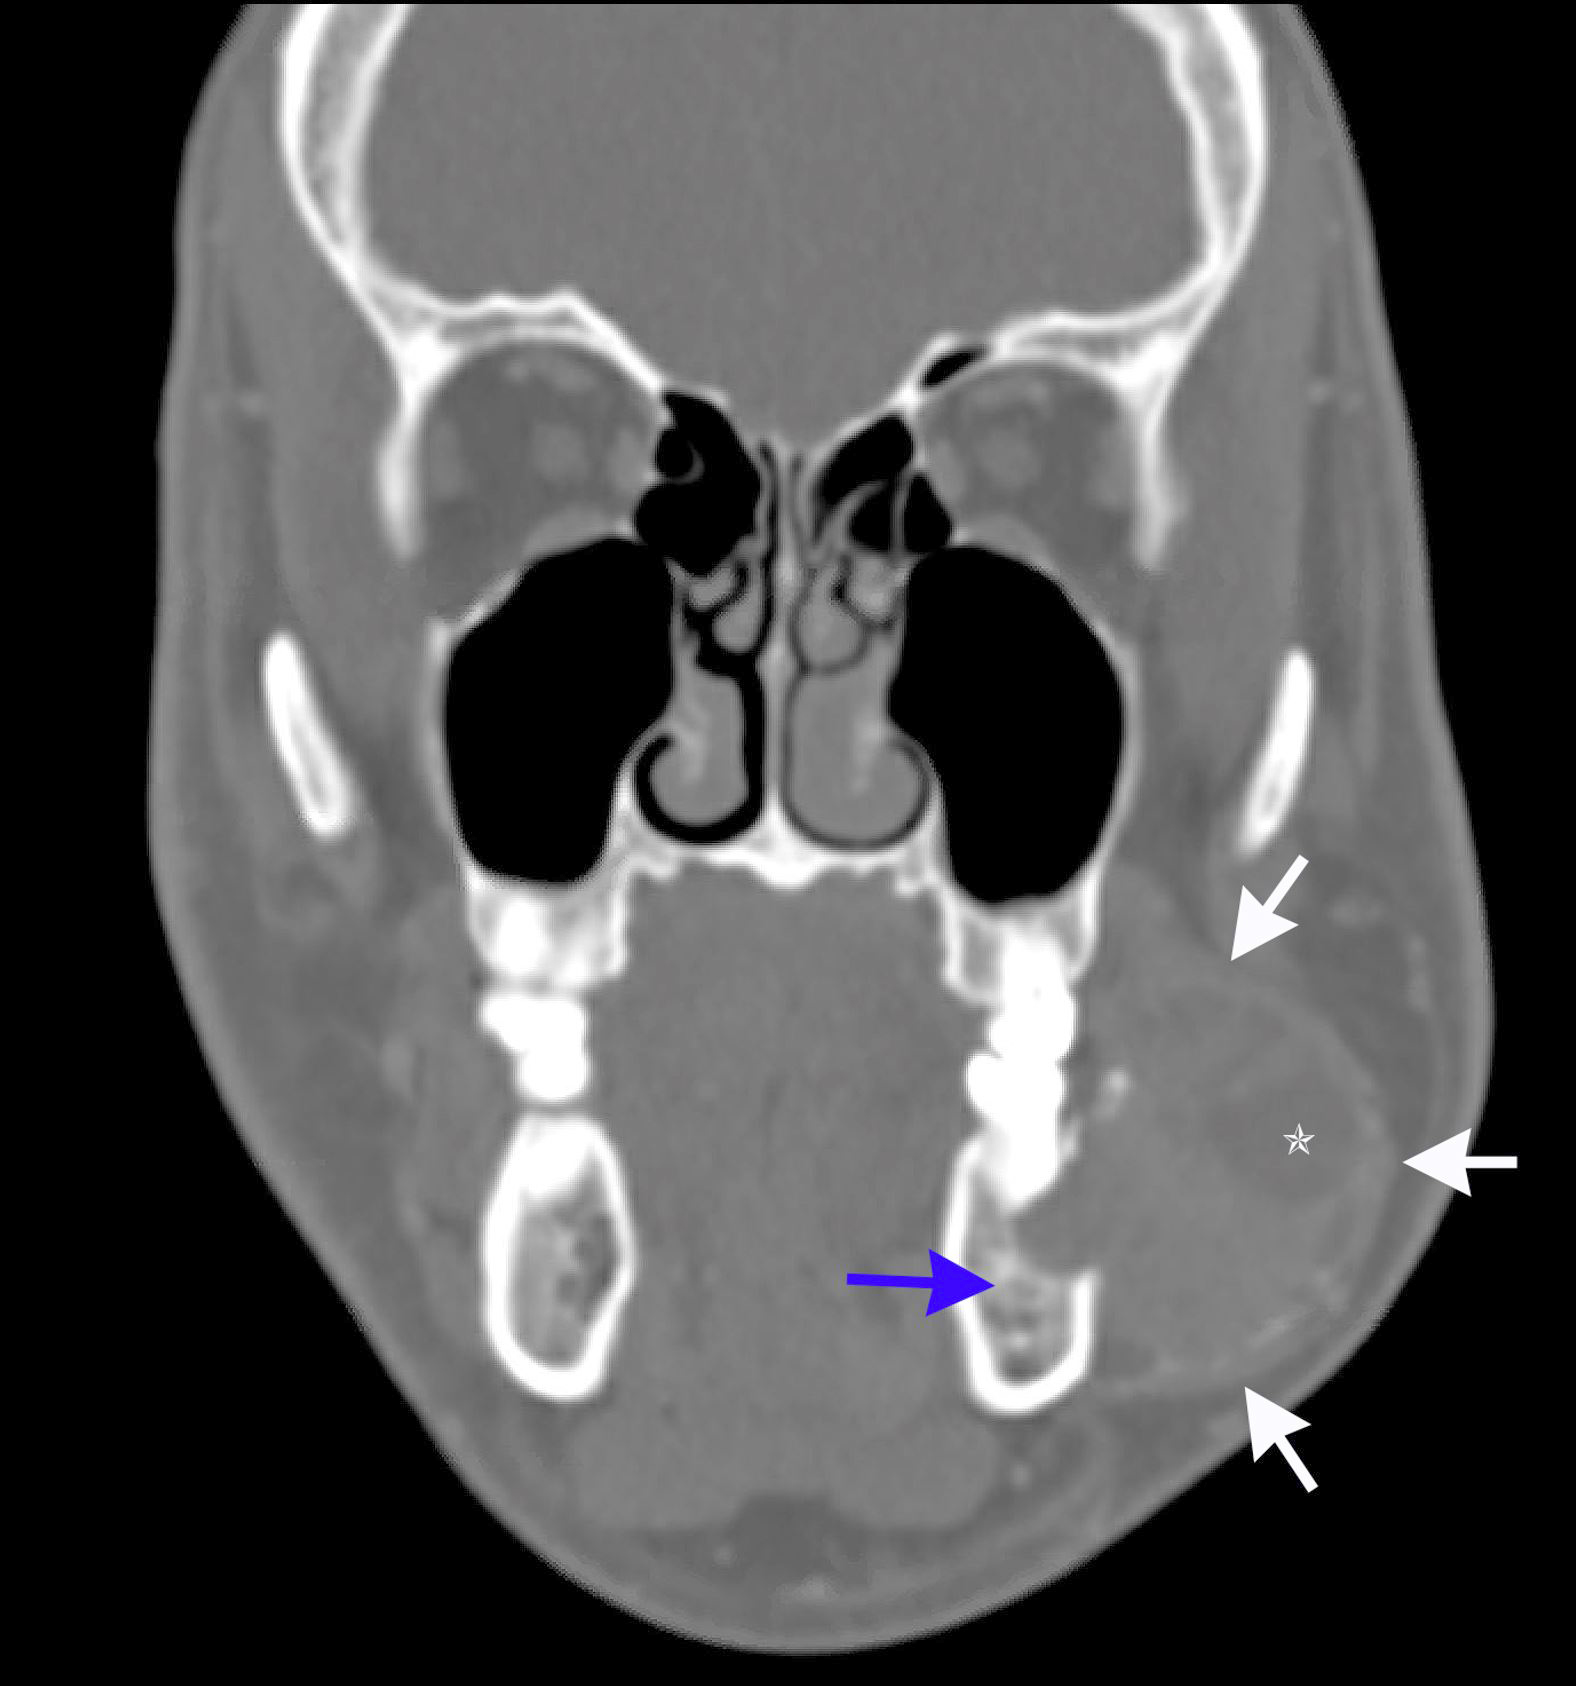

Radiology description

- Ameloblastoma, conventional

- Expansile multilocular radiolucency, well defined, corticated border

- Some cases exhibit classic soap bubble appearance

- May or may not be associated with impacted tooth / teeth

- Resorption or displacement of tooth roots

- Reactive bone formation may occur, most commonly in desmoplastic ameloblastoma, which may resemble a fibro-osseous lesion radiographically due to the presence of osteoplasia

- May have a unicystic radiographic appearance on plain images; requires microscopic examination for distinction from ameloblastoma, unicystic type (Dentomaxillofac Radiol 2018;47:20170288)

- Ameloblastoma, unicystic type

- Unilocular radiolucency, well defined, corticated border

- Often associated with an impacted tooth, specifically mandibular third molar

- Root resorption may occur

- Cortical perforation in 33% of cases

Radiology images